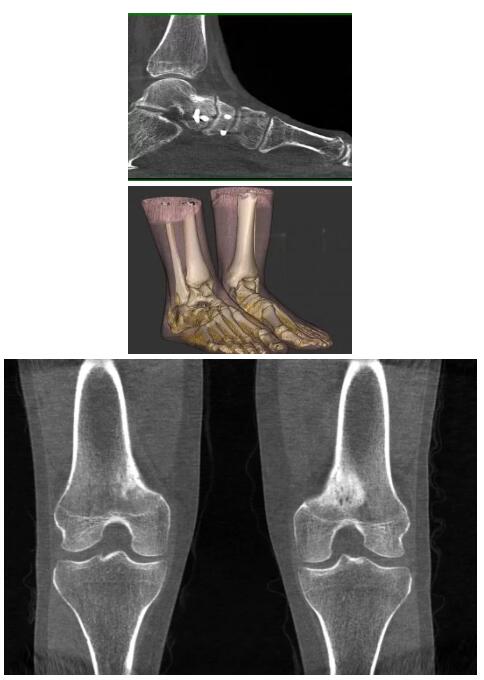

比如上面這款專用于足部和踝部掃查的CT成像系統(tǒng),患者在進行CT掃查時只需要站在上面即可,雙腳站或者單腳站都可以,當然,如果患者不是那么方便站著做完CT掃查,也可坐在上面。

這款CT掃查系統(tǒng)自帶屏蔽裝置,它的體積非常小,僅需要極小的空間即可,并不像常規(guī)CT那樣需要一間單獨的檢查室。此外,這種CT掃查的速度非???,僅需30秒左右可以完成檢查,輻射劑量相對常規(guī)的CT要少許多,尤其適合醫(yī)院的骨科使用。

而患者站著做足部或者踝部做CT檢查還有個好處是,可以檢查患者在負重的情況下,骨關節(jié)的真實情況,而躺著做CT掃查時未必能看出來。負重CT掃查特別是對于受傷的運動員或者舞蹈員來說意義更大,能夠更準確地評估傷情,幫助他們盡早復原。

以下是這些“特立獨行”的CT所拍出來的圖像: